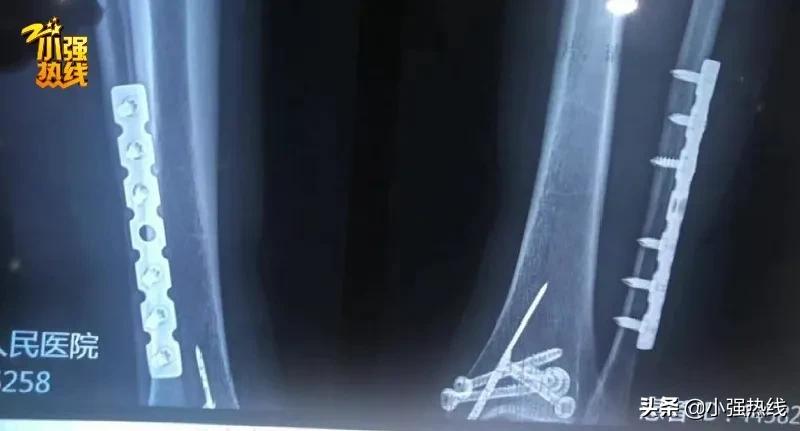

在泰国紧急处理后,吕女士第二天就回了国,随后住进了嘉兴桐乡第一人民医院,接受手术,在伤处植入钢板,花费了18000多元。

之后,吕女士一直在家进行康复,直到今年8月份才取出钢板,又花费了7000多元,还留下了一道15厘米的疤痕。